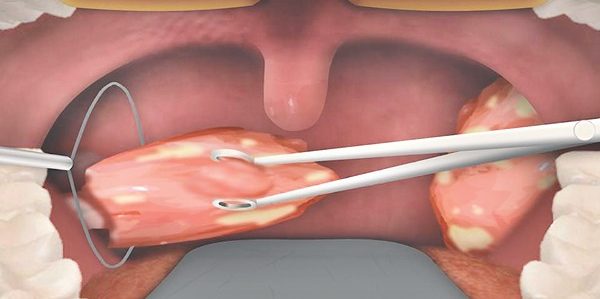

Gırtlak (Larinks) Kanseri Nedir? Gırtlak kanseri, gırtlaktan köken alan bir kanser türüdür. Gırtlak, yutma işlemi sırasında nefes borusunu koruyan, dışarıdan solunum yoluyla alınan havanın akciğere ulaşmasını sağlayan ve barındırdığı ses telleri vasıtasıyla ses oluşumunu sağlar. Tıp dilindeki adı larinks kanseri olan gırtlak kanseri, baş boyun kanserleri arasında en sık görülen kanser türlerinden biridir. Gırtlak Kanseri…

- Larenjit: Gırtlak iltihabıdır. Ses kısıklığı, boğaz ağrısı gibi belirtilerle ortaya çıkar.

- Boğaz Kanseri: Boğaz bölgesinde gelişen kanser türlerini ifade eder.